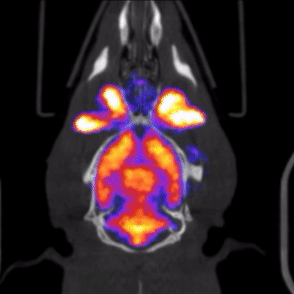

null Mediso nanoScan PET/CT

| Le scanneur PET/CT permet de réaliser de l'imagerie fonctionnelle et moléculaire à l'aide de radio-traceurs émettant des positons. |